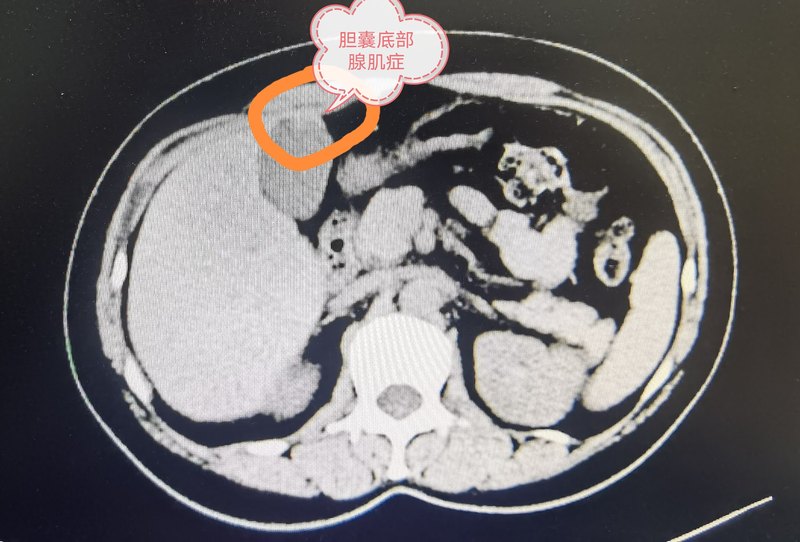

- 膽囊底腺肌癥之保膽

膽囊底部腺肌癥保膽手術(shù) 膽囊腺肌癥局限于膽囊底部,這種情況并不少見。往往發(fā)現(xiàn)時會有人告訴你可能是腫瘤,恐懼!?無助!?馬上聯(lián)系醫(yī)院,手術(shù)。切除——,病理報告膽囊腺肌癥。不是癌,萬幸!? 那么這種情況能否不切除膽囊呢?當(dāng)然可以! 我們在腹腔鏡下完整切除膽囊底部,行冰凍病理檢查明確膽囊腺肌癥,之后縫合膽囊切口,保留膽囊。 多年臨床觀察發(fā)現(xiàn)效果良好。